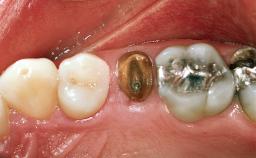

Replacement of a Maxillary Right Central Incisor Using an Early Loading Protocol

A healthy 26-year-old woman was referred for evaluation and treatment of her failing maxillary right central incisor (tooth 11). She reportedly traumatized the tooth at about age 9 and subsequently had repeated conventional and surgical endodontic procedures and fixed restorations. Despite these procedures, she had recurrent fistulas in the apical mucosa and a mid-facial pocket of 7 mm with suppuration. All other sites on the tooth probed 3 mm without inflammation. She presented with a medium biotype with triangularlyshaped teeth and a moderately high smile line, showing all of her papillas and a few millimeters of marginal gingiva in a full smile.Ceramic veneers were present on teeth 12, 21, and 22, and they were known to be somewhat bulky, eventually requiring replacement. She had a strong desire to avoid additional tooth preparation and would not consider a fixed dental prosthesis to replace tooth 11.

Prosthesis Type FDP

Loading Protocol Conventional or early